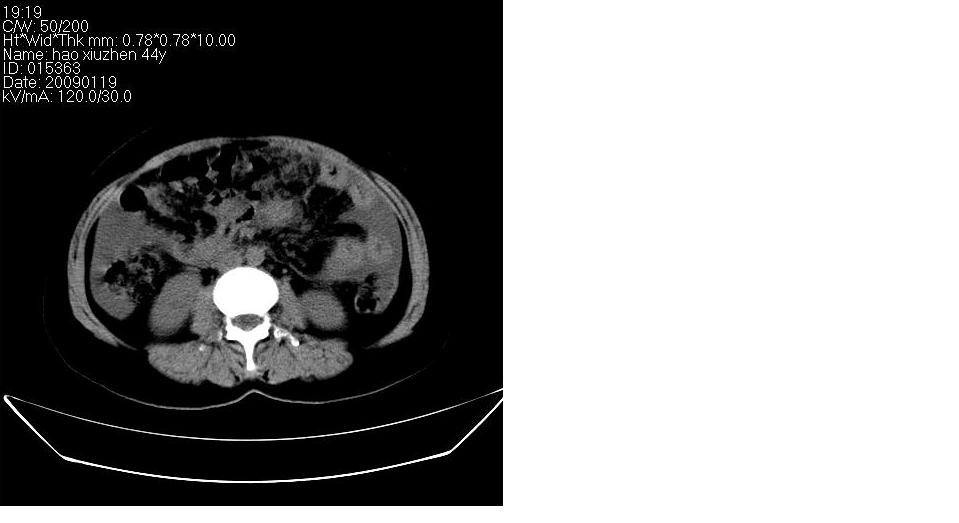

以下是引用zbp537在2009-1-19 14:09:00的发言:[br]从这个平扫图像上看,只能考虑:1、胸腹水。2、脾脏包膜下弧形高密度影,疑出血,建议复查。[br]既然腹水中有恶性细胞,建议行腹部ct增强扫描及胸部扫描。

以下是引用随光逐影在2009-1-19 15:47:00的发言:[br]1)不排除胃癌可能;建议行胃镜检查。2)腹水。3)右侧胸腔积液。

以下是引用jiangjing在2009-1-19 18:21:00的发言:[br]1 网膜污垢征---肿瘤网膜转移.2)腹水。3)右侧胸腔积液